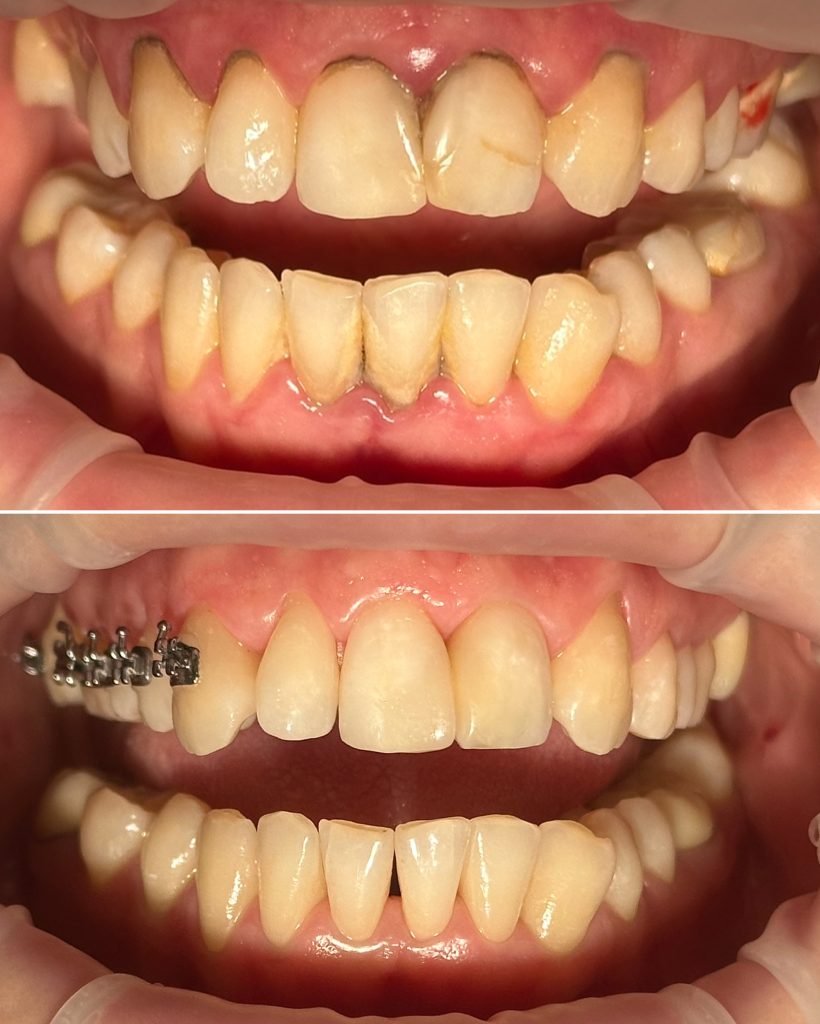

• Профессиональная гигиена полости рта и подбор индивидуальных средств гигиены, профилактика стоматологических заболеваний

2024 год – «Системный подход к лечению пациентов с заболеваниями пародонта. Ручные инструменты и SRP-терапия» Юрий Гринюка